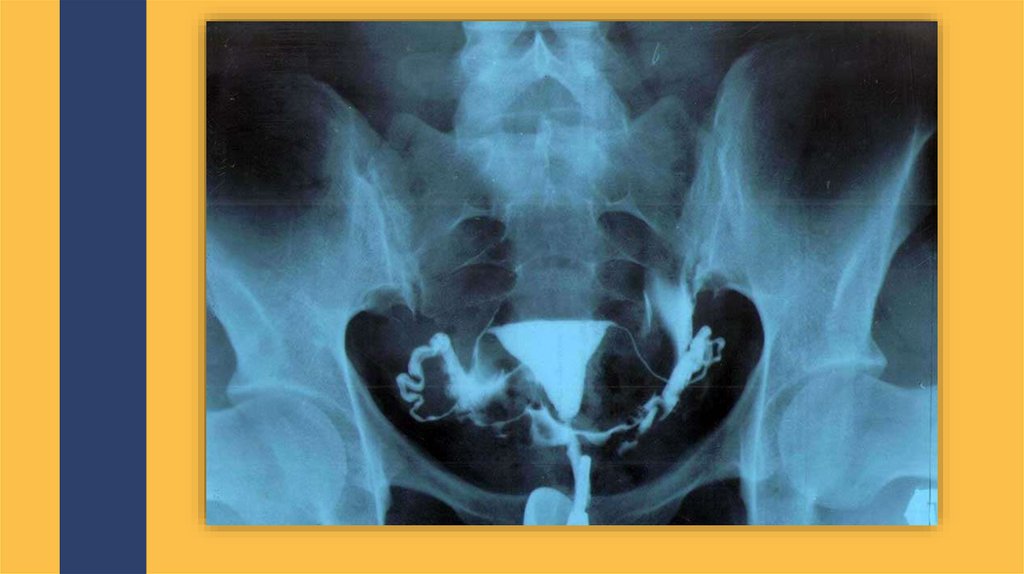

Диагностика

Инструментальные ис-ния